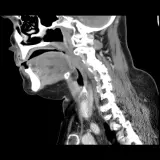

PACS์—์„œ ๊ธฐ๋Œ€ํ•  ์ˆ˜ ์žˆ๋Š” ๋ชจ๋“  ๋„๊ตฌ๋ฅผ ๊ฐ–์ถ˜ ์™„์ „ํ•œ ์ธํ„ฐ๋ž™ํ‹ฐ๋ธŒ ์ฆ๋ก€ — ์Šคํฌ๋กค, ์œˆ๋„์šฐ ์กฐ์ ˆ, ํ™•๋Œ€/์ถ•์†Œ, ํŒจ๋‹, ๊ณ„์ธก, ROI, ์ „์ฒด ํ™”๋ฉด ๋ชจ๋“œ๊นŒ์ง€ ์ง€์›ํ•ฉ๋‹ˆ๋‹ค.

์‹ค์ œ PACS ์›Œํฌ์Šคํ…Œ์ด์…˜์ฒ˜๋Ÿผ ์Šคํฌ๋กค, ํŒจ๋‹, ์œˆ๋„์šฐ ์กฐ์ ˆ, ํ™•๋Œ€/์ถ•์†Œ๊ฐ€ ๊ฐ€๋Šฅํ•ฉ๋‹ˆ๋‹ค